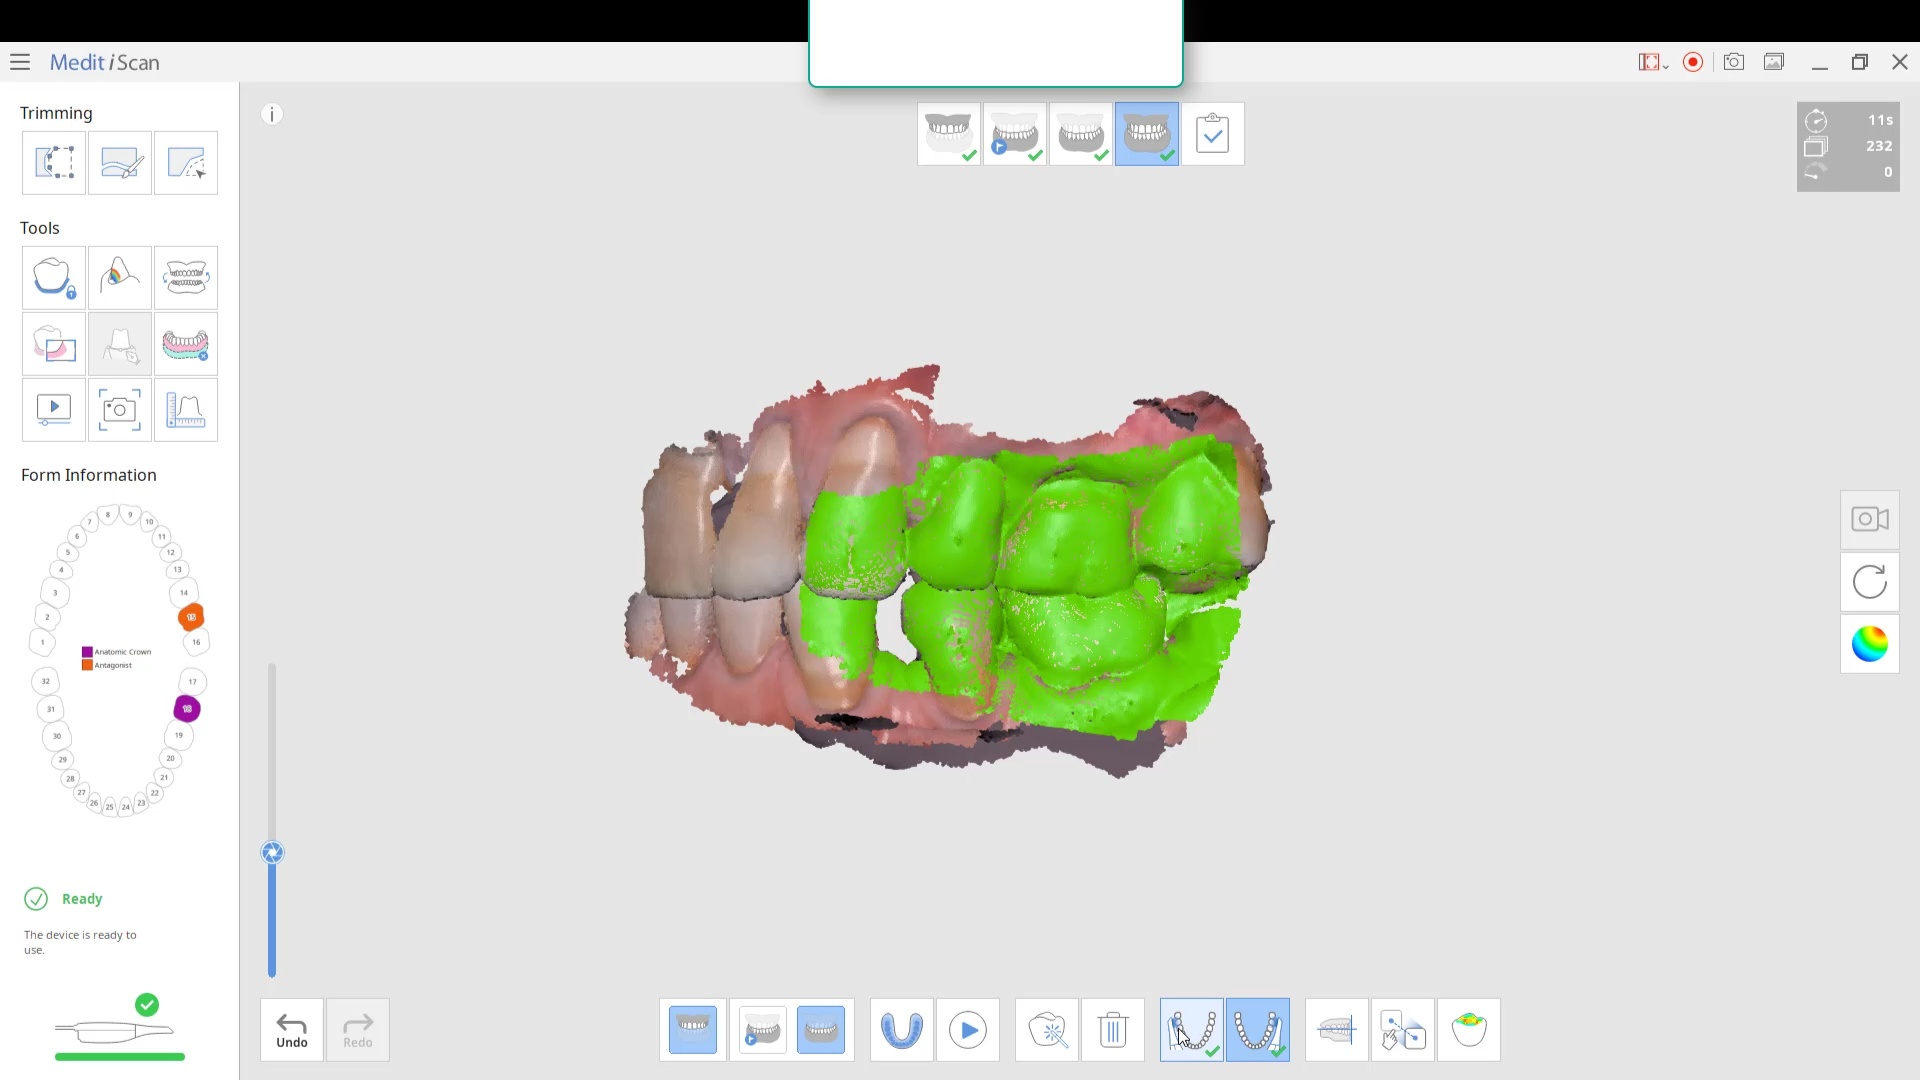

For our advanced users who mill in house or what to speed up their digital impressions we advocate taking advantage of digital dentistry’s unique features that allow you to take impressions over a period of time and segments, building larger models over different sequences and time. In this particular case we have two molars in the lower left quadrant that warranted replacement. The traditional method would be to prep both, isolate both, retract both, and take your final impression, but we will approach this as if there are two separate patients involved

For the second molar, we will take advantage of the anesthesia time and capture the first bite, the opposing, the pre-existing situation and then crop out the preparation area digitally. Once the tooth is prepared, we will check for proper reduction. We will then take the second bite to verify the vertical dimension has not changed.

While the second molar is being designed and milled in the first case, we will launch a second window by cloning the first case. All the data remains the same and this time we crop out the first molar digitally and protect the rest of the arch. Once the first molar is isolated, it is digitally captured and then designed and milled.